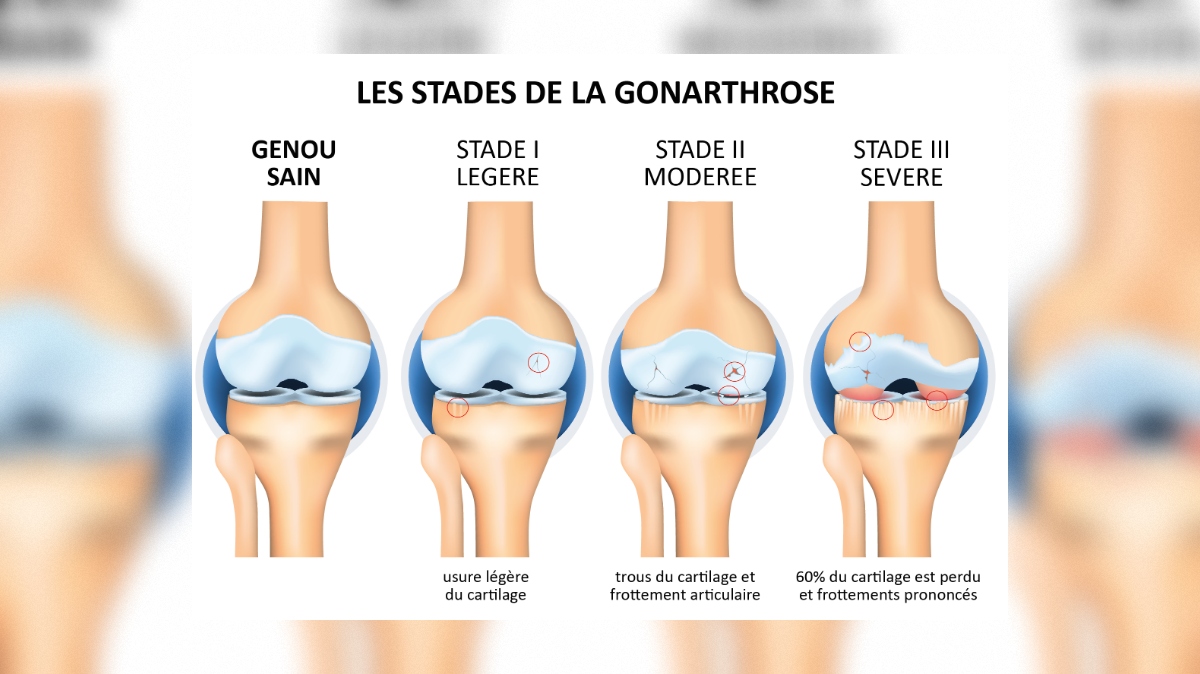

Arthrose : comprendre et agir

Guides pratiques sur l'arthrose du genou et de la hanche, et outil d'auto-évaluation rapide.